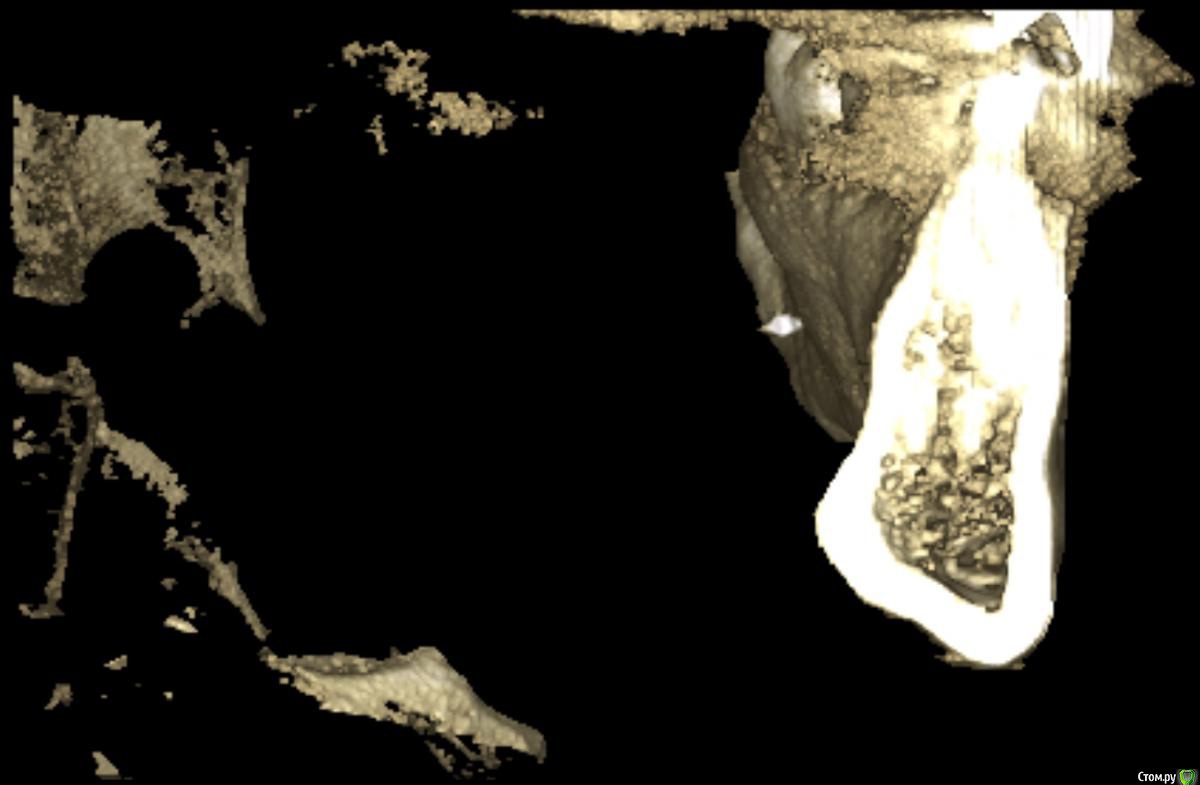

medbratec Опубликовано 13 октября, 2016 Автор Поделиться Опубликовано 13 октября, 2016 Я вас прекрасно понимаю. Был бы специалистом, то так сразу и сделал. Просто не знаю, что конкретно и под каким углом показывать. Сделал несколько скриншотов. Напишите, если они окажутся не слишком информативны. Ссылка на комментарий

medbratec Опубликовано 13 октября, 2016 Автор Поделиться Опубликовано 13 октября, 2016 Ссылка на комментарий

IvanK Опубликовано 14 октября, 2016 Поделиться Опубликовано 14 октября, 2016 скорее всего , это пломбировочный материал, лежит он не в костной ткани, а в мягких тканях, если не беспокоит, то можно не трогать 1 Ссылка на комментарий

red_butler Опубликовано 17 октября, 2016 Поделиться Опубликовано 17 октября, 2016 если это пломбировочный материал то на снимках "до" он должен быть, но я вижу там что то металлическое 2 Ссылка на комментарий

kramer Опубликовано 22 октября, 2016 Поделиться Опубликовано 22 октября, 2016 если это пломбировочный материал то на снимках "до" он должен быть, но я вижу там что то металлическоеЧисто по снимку похоже на кончик твердосплавного бора. ИМХО. Ссылка на комментарий